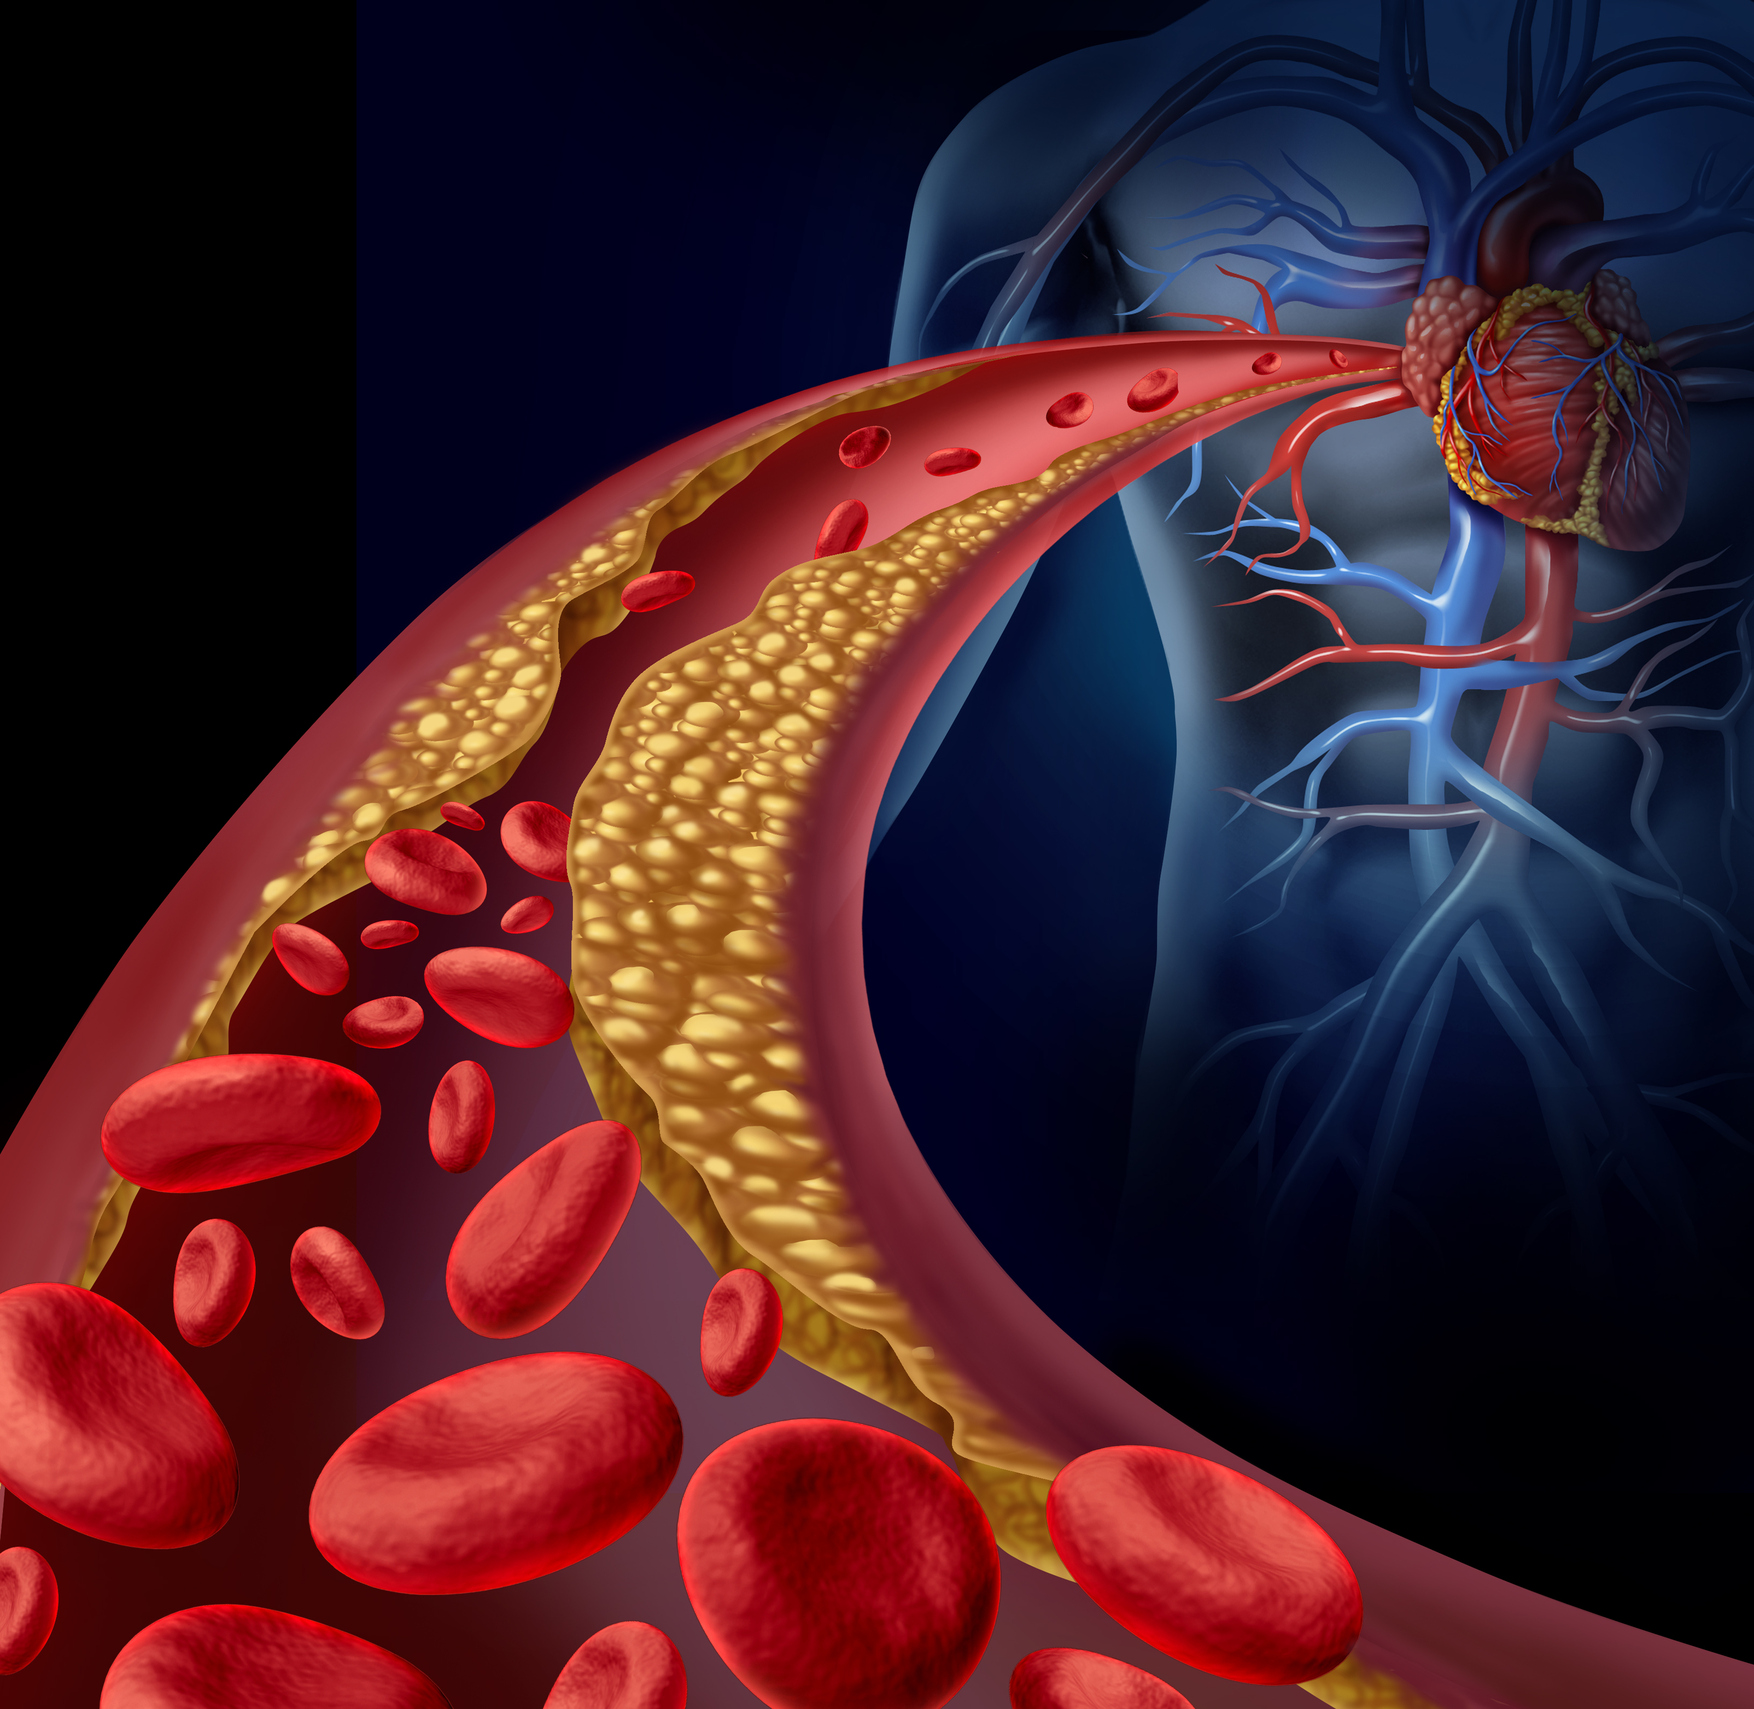

Холестерин в организме: влияние и функции (схемы и диаграммы)